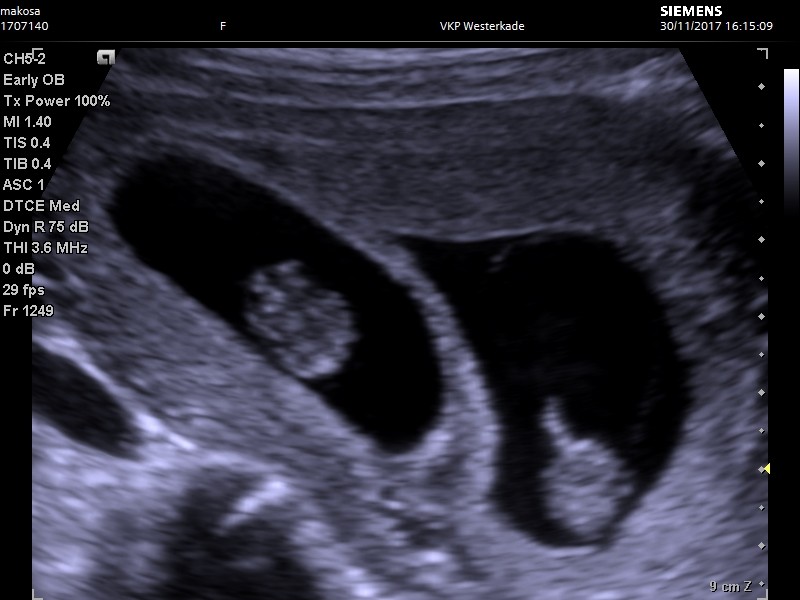

chcialabym do Was dołączyć. Widzę, że wy już w zaawansowanych ciążąch, a ja dopiero 10 tc, wczoraj pierwsze USG i zobaczyliśmy dwójkę :)

Niestety jeszcze nie znam jeszcze szczegółów, bo byłam u położnej, która powiedziała, że nie zna się na bliźniachach i dowiem się więcej dopiero jak pójdę do specjalisty ( mieszkam w Holandii, tutaj sytem się sporo różni).

Niestety udało jej się mnie nastraszyć. Zmierzyła bąble, jeden ma 3,5 cm, a drugi 2,8, czyli jeden 10 tc+1 dzień, drugi 9 tydzień - 3 dzień. Usłuszałam, że to niedobrze i jest spore prawdopodobieństo że jeden nie przeżyje. Miałyście może takie sytuacje? Naprawdę jest tak źle?

Ciężko jej szło to mierzenie, mam nadzieję, że się trochę pomyliła :)

Witamy w naszym gronie:) na Twoim miejscu jak najszybciej zarejestrowalabym się do lekarza, żeby nie dokładać sobie niepotrzebnych stresów. Zresztą sama położna powiedziała, że nie zna się na bliźniakach więc niekoniecznie dobrze je zbadała. A tak poza tym to w większości przypadków nasze dzieciaczki różnią się wielkością. Jaka to jest ciąża? Jeśli dobrze widzę na zdjęciu to dwudowodniowa i każde dziecko ma swój domek;), w takich przypadkach różnica w wielkości płodów nie jest aż tak istotna. Sama mam ciążę 2k2o i między dziećmi na USG wychodzi ok 3-5 dni różnicy.

Również polecam Ci jak najszybciej wybrać się do lekarza, żeby niepotrzebnie się nie stresować. Na moje oko ciąża wygląda na rozwijająca się prawidłowo i wcale nie ma takiej różnicy w wielkości fasolek - różnica wynika pewnie z błędu pomiaru i tego, że położna nie ma takiej wprawy i wiedzy jak lekarz.

Chciałam Cię tylko uprzedzić, że mi na pierwszej wizycie pani doktor rowniez powiedziała, żeby liczyć się z tym, że jeden z dwóch bliźniaków może się jeszcze na tym etapie wchłonąć/obumrzeć i jest to jak najbardziej normalne. Tak się po prostu czasami dzieje, ale oczywiście życzę Ci żebyś na kolejnym badaniu zobaczyła 2 bijące serduszka :tak: